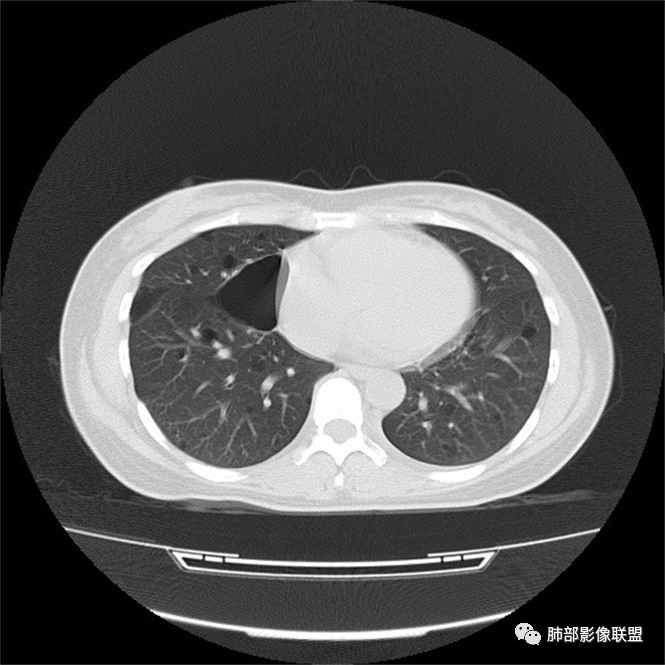

双肺弥漫囊腔,累及肋膈角,囊腔形态相对规则单一。

CT平扫示双肺弥漫分布大小不等囊状薄壁透光区,无内、中、外带分布差异,间质稍示增厚。拟LAM

中年女性育龄期妇女,咳嗽气喘,无吸烟史,有苯吸入史。影像:双肺弥漫均匀小囊腔,无明显分布优势,囊腔形态欠规则,壁薄,部分囊腔边缘血管征,伴双肺弥漫磨玻璃影,无结节,考虑lam,鉴别苯中毒肺损伤,囊腔多有分布优势,小叶中心分布为主,形态规整等

女,46,活动性气喘1年。苯吸入史半年。胸部CT:两肺弥漫囊腔,上至肺尖,下至肋膈角,形态类似小囊腔。考虑:LAM,鉴别LIP,BHD,PLCH等。

CT表现:双肺弥漫大小不等的薄壁囊腔,囊壁<2mm,外形规则,血管影多位于囊腔周围,囊腔之间肺组织正常,随着疾病进展到晚期,囊腔变大、增多,不可胜数,囊腔可融合成较大的囊,与肺气肿相似,形成间质性肺纤维化。部分病例可出现结节影。